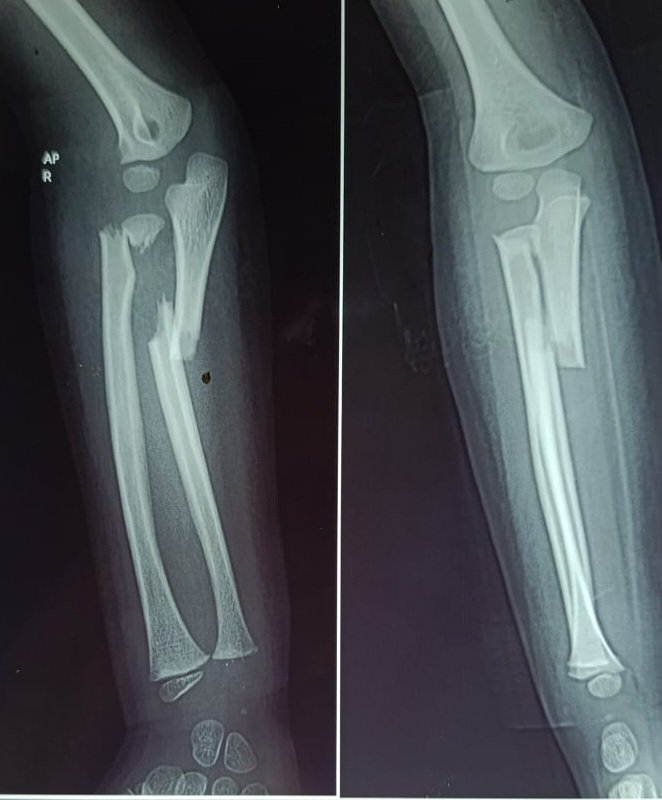

MSK Teaching Room@mskteachingroom·

28-year-old went for a jog and came back with more than just a runner’s high. 👀 What’s the key abnormality you spot here? 🧐🔥 Drop your diagnosis below! ⬇️ #Radiology #MedTwitter #FOAMrad #Quiz